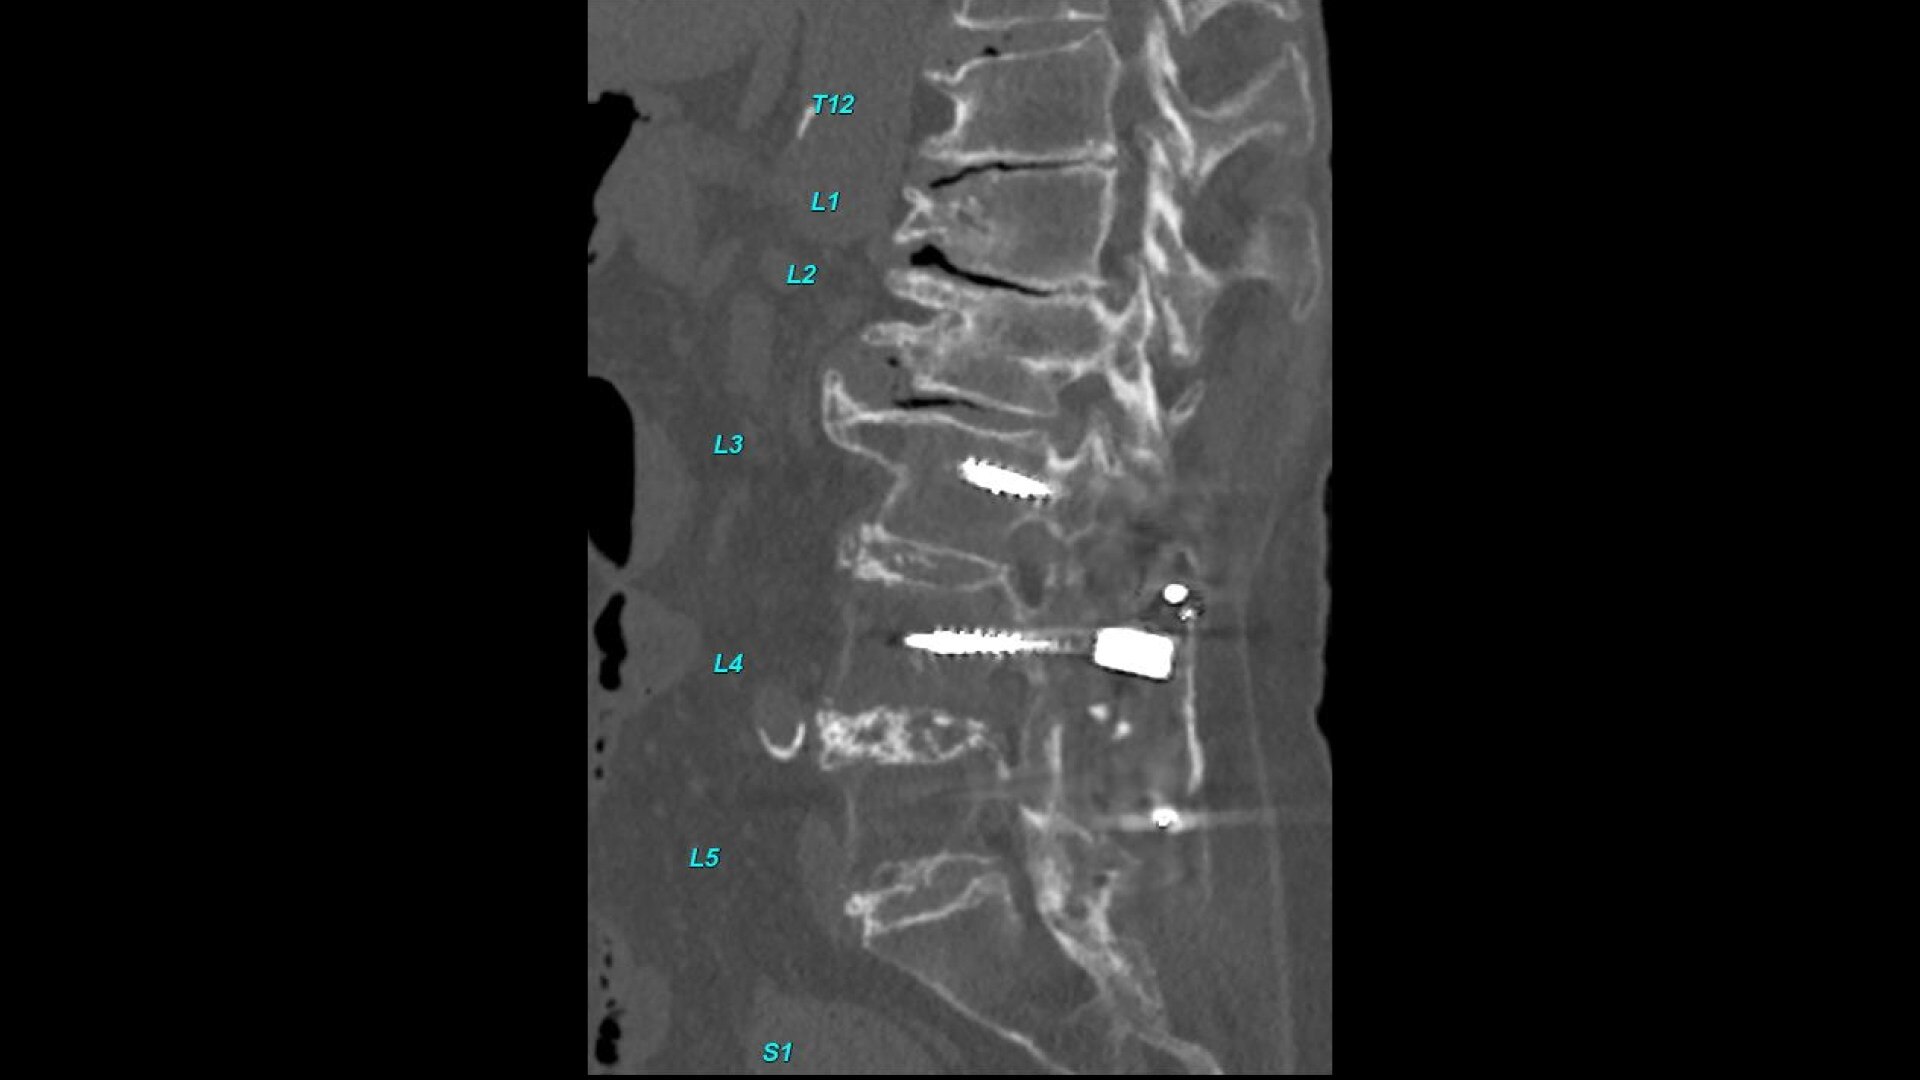

Bone VCAR

Spine assessment with deep-learning based CT application.

Automated spine identification and labelling.

>90% labeling accuracy based on Deep learning algorithm trained on global datasets acquired with a broad range of acquisition parameters.

• Automated spine labeling

• Automated generation of a 3D trace to generate oblique and straightened reformat views

• Automated generation of oblique views perpendicular to vertebral bodies and disc spaces

• Easily edit the centerline to ensure accurate placement in the most challenging cases

• Accessible for any exam type: trauma, oncology, dedicated spine, general imaging